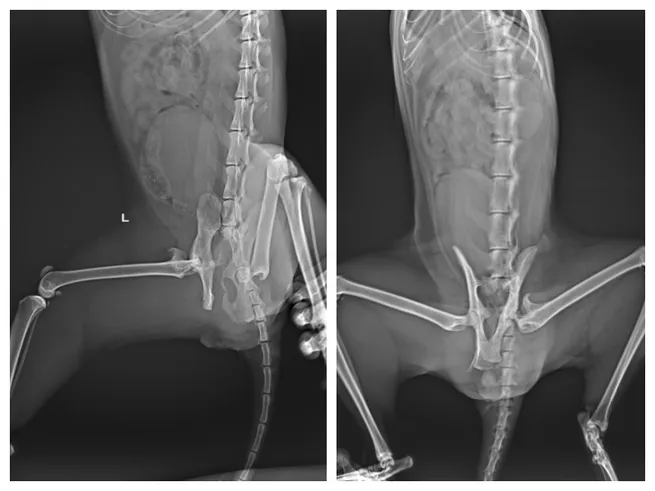

Kolejnym, niezbędnym etapem diagnostyki jest wykonanie zdjęć rentgenowskich. RTG pozwala dokładnie określić rodzaj złamania, jego lokalizację oraz stopień przemieszczenia kości. Na podstawie tych informacji weterynarz może zaplanować odpowiednie leczenie i oszacować, jak długo zrasta się złamanie u kota w danym przypadku. W niektórych sytuacjach może być konieczne wykonanie dodatkowych badań, takich jak tomografia komputerowa, szczególnie przy skomplikowanych złamaniach miednicy czy kręgosłupa.